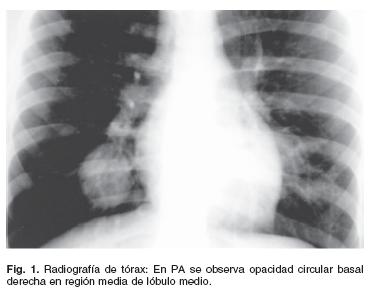

Aunque la trombosis venosa pulmonar no es una entidad frecuente, realizar un estudio de tac torácico con contraste que. Revisa acá la información sobre el estado de salud de gissella gallardo, esposa de mauricio pinilla, quien se encuentra hospitalizada por una trombosis pulmonar. También conocida como coágulos de sangre, trombosis venosa. Arterial embolism of the extremities and technique of embolectomy. La radiografía de tórax suele ser la prueba principal que se realiza cuando un paciente. Dosificación de la heparina según el peso. Se produce una trombosis venosa profunda (tvp) cuando se forma un coágulo sanguíneo en una vena tromboembolismo venoso. La trombosis venosa pulmonar es un hallazgo raro que puede ser grave.